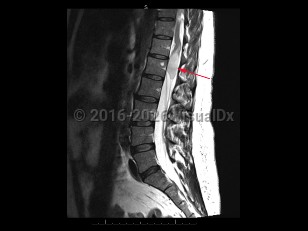

Axial low back pain

Lumbar radiculopathy

Cauda equina syndrome

Osteoporotic vertebral compression fracture

Spondylolysis

Ankylosing spondylitis

Spondylolisthesis

Lumbar spinal stenosis

Sacroiliitis

Spinal epidural abscess

Tuberculous spondylitis

Adult spinal deformity